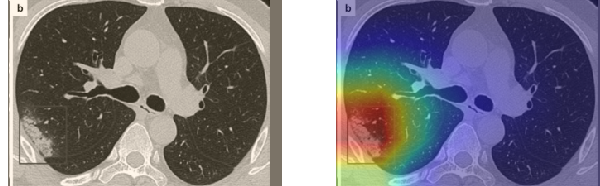

In order to make our models more transparent and provide detailed visual analysis, we present the Grad-CAM localization maps obtained by different models. We consider CT images with COVID-19 abnormalities from the test set of each dataset and highlight the important regions considered for the prediction. For the SARS-CoV-2 dataset we use the Inception V3 model. Figure 13 shows the original CT images and their localization maps. Our model is capable to detect regions that show abnormalities in the CT scans.

In a similar way, we consider classifying the test CT scans from the COVID-19 dataset by the DenseNet169 model and highlight the important regions considered for predictions. We present the original CT images and their localization maps in Figure 13. We can also see that our model is capable to detect the COVID-19 related regions as marked (small square in some images) by expert radiologists.

A wide variety of typical and atypical CT abnormalities have been reported for COVID-19 patients in various studies [58, 59]. So, we tested our models on external CT images extracted from these two publications as they feature typical findings of COVID-19 pneumonia marked by specialists. In order to make sure that not any of the extracted images are unintentionally included in our datasets, specifically the COVID19-CT dataset, we use the model trained on the SARS-CoV-2 dataset. First, the InceptionV3 model is employed to classify the extracted CT images. The model is able to correctly classify the given CT images as COVID-19. Second, in order to interpret the model’s generalization capabilities, we apply the Grad-CAM technique to visualize the regions of abnormalities that are considered. By assessing the different CT images in Figure 15, we can see that the model accurately localizes the disease-related regions. Even more interesting is the fact that the model ignores any specific marks in the images like letters and only localizes the COVID-19 related regions. These visual explanations show the success of our models to learn relevant, generic visual features related to COVID-19 and are capable to correctly classify CT images outside the datasets on which they are trained.